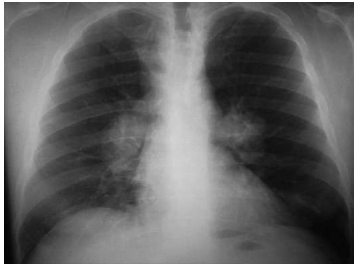

Caso clínico hipotético para a questão.

Uma paciente de 35 anos de idade dirigiu-se ao pronto

atendimento com queixa de tosse há 4 meses. Ela

relatou fadiga, astenia e mal-estar desde o início do

quadro. Também queixou-se de febre baixa intermitente,

oligoartrite aguda simétrica em tornozelos e lesões

nodulares e dolorosas em região pré-tibial de membros

inferiores com perda de peso não mensurada.

Considere-se a imagem a seguir.

Foi realizado eletrocardiograma do paciente e solicitada troponina. Com base no quadro clínico e na imagem apresentada, assinale a opção que apresenta a conduta adequada.